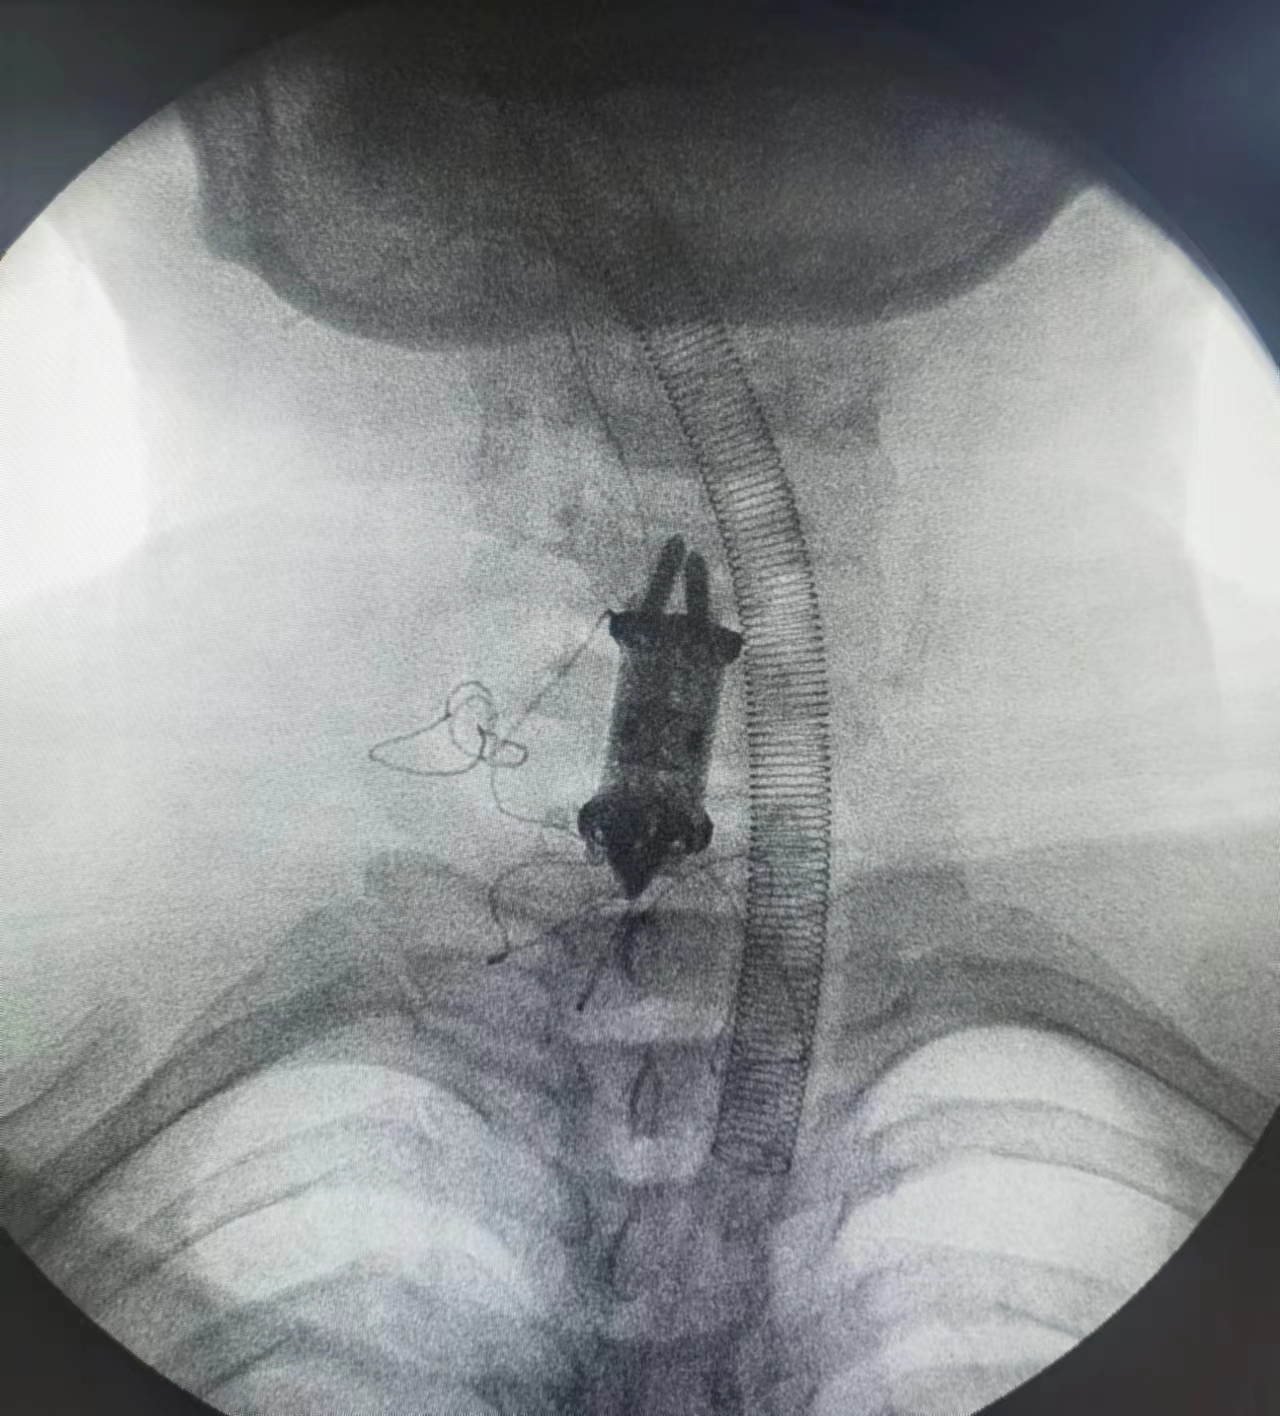

2023年2月1日一早,马莹被推进手术室。刘忠军教授主刀,经颈前路,切除了她的第5-6节、第6-7节颈椎间椎间盘,将脱出的髓核摘除,使硬脊膜囊充分减压。随后,全切第6节椎体,将一枚自稳型3D打印的钛合金微孔结构的人工椎体,稳稳地植入其中。上下端固定,透视显示人工椎体位置满意。手术顺利完成。

马莹的手术是“一体化零切迹”椎体置换,手术步骤减少、时间缩短、固定可靠性也大大增强,有效避免了术后因食道受挤压而可能导致的吞咽困难。